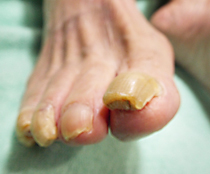

魚の目の処置

施術前

施術後